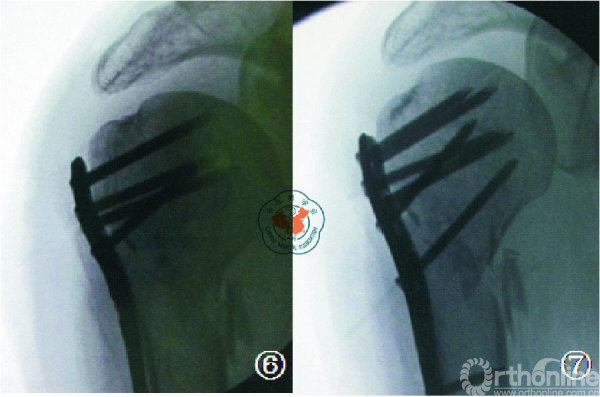

该理论认为:肱骨头下方内侧皮质的支撑作用是防止术后肱骨头塌陷的主要支撑作用。在复位和固定的时候,该部位必须作为重点修复和复位的部分,予以足够的重视。目前认为,在肱骨近端骨折的复位和固定中,肱骨头内下方皮质支撑作用十分重要,应当予以充分复位及支持。如果内侧皮质支撑结构破坏广泛,可采用长短腓骨髓腔内结构性植骨以重建内侧支撑。如内侧皮质结构尚完整,但出现了内侧的阴性支撑,则需要使用肱骨距螺钉斜跨干骺端与后内侧皮质以行支撑(图6、7)。在此强调的是,内侧皮质缺损是肱骨头内翻畸形的力学不稳定因素,但在治疗中首先应将肱骨头复位至正常头干角,再行稳定固定。如复位不良,结构性的支撑植骨只能预防肱骨头的进一步内翻塌陷而并不能起到复位作用,而肱骨距螺钉对内翻畸形的肱骨头则并无保护作用。

图6示内侧皮质粉碎的肱骨近端两部分骨折(外科颈);

图7钢板固定后见内侧皮质不连续,肱骨近端骨折在内侧无嵌 插,属阴性支撑。经philos钢板“E”孔打入肱骨距螺钉,起内侧支撑作用。